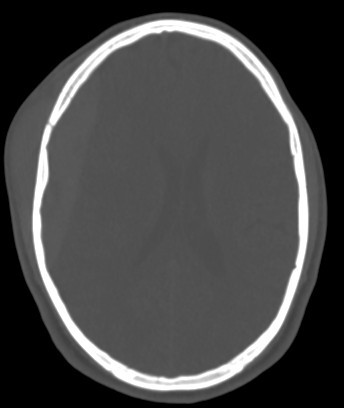

brain CT scan

brain CT scan History

A brain CT scan, also known as a computed tomography scan or CAT scan, is a non-invasive imaging procedure that uses X-rays to create detailed cross-sectional images of the brain and surrounding structures. It's a common diagnostic tool for evaluating head injuries, strokes, brain tumors, and other neurological conditions. Here's a more detailed explanation: What it is: A brain CT scan uses a series of X-ray beams that rotate around the head, capturing multiple images from different angles. These images are then processed by a computer to create detailed cross-sectional views of the brain, allowing doctors to visualize the brain's structures and identify any abnormalities. The scan can be performed with or without contrast dye, which helps to highlight certain tissues and blood vessels for better visualization. Why it's used: Traumatic brain injuries: CT scans are often the first imaging test used to assess the extent of head injuries and identify potential fractures, bleeding, or swelling. Stroke: CT scans can quickly identify whether a stroke is caused by a blood clot (ischemic stroke) or bleeding (hemorrhagic stroke), guiding appropriate treatment. Brain tumors: CT scans can help detect and assess the size and location of brain tumors. Other neurological conditions: CT scans can also be used to diagnose conditions like hydrocephalus (excess fluid in the brain), aneurysms (bulges in blood vessels), and certain types of dementia. Guiding procedures: CT scans can be used to guide biopsies or other procedures involving the brain. What to expect during the procedure: You will lie on a table that slides into the CT scanner, which is a large, doughnut-shaped machine. The scan itself is painless, but some people may experience slight discomfort from lying still on the hard table. If contrast is used, you may feel a warm or flushing sensation, or a metallic taste in your mouth. The scan typically takes only a few minutes. Risks and Precautions: CT scans involve exposure to radiation, but the risk from a single scan is generally considered low. If you are pregnant, it's important to inform your doctor, as alternative imaging methods may be considered to avoid exposing the fetus to radiation. If you have any allergies, particularly to contrast dye, make sure to inform your doctor.